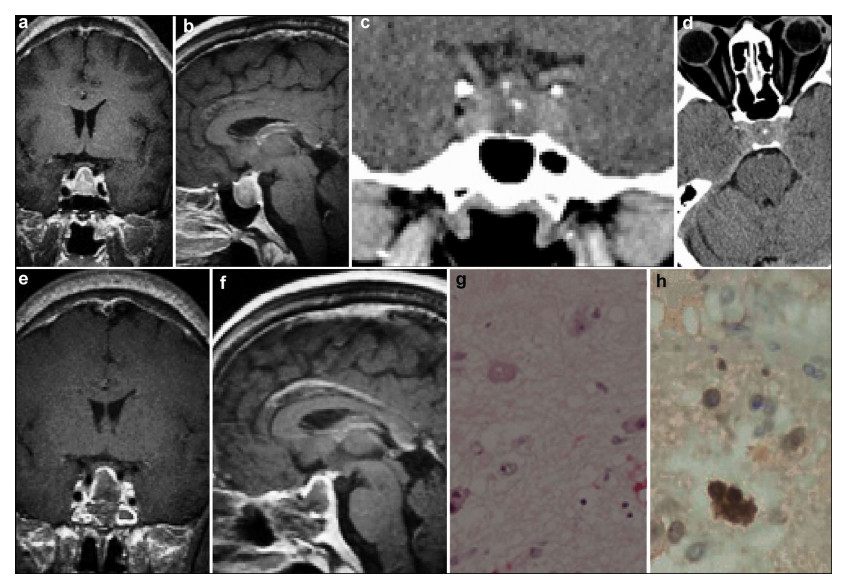

3 Clinical findings 3.1 Case oneA 37-year-old woman complained of irregular menses for 3 years, and headache with a visual deficit for 1 year. Results of general physical examination and neurological examination were unremarkable. Galactorrhea was not demonstrated on pressing the breast. Neuro-ophthalmological examination disclosed bitemporal visual field defect with a slight visual acuity decline, while the fundi were normal. Magnetic resonance imaging (MRI) and computed tomography (CT) demonstrated an enlarged sella turcica containing an intrasellar mass with a suprasellar extension measuring 28 mm × 20 mm × 18 mm (Figures 1a-1f). The endocrinological evaluation revealed an elevated serum level of prolactin (PRL) of 64.83 ng/mL (reference range, 2.5-17.0 ng/mL); other parameters were within the normal range (Table 1). The patient underwent pure transnasal transsphenoidal endoscopic surgery and a tumor mass occupying the sellar cavity was completely removed. The diaphragm of the sella turcica was intact. Results of the postoperative immunohisto-chemical staining revealed SYN (+), CK8/18 (+), NSE (+), and GFAP (-) (Figures 1g and 1h). The diagnosis by the pathologists was hypothalamic hamartoma ganglion cell tumor combined with pituitary adenoma. The postoperative period was uneventful. Endocrine investigations were performed at 3 months, 6 months, 1 year, and then annually after surgery. All hormone values were normal. At present, the patient has experienced a follow-up period of 9 years, and no signs of recurrence had been detected.

| Figure 1 Case 1. The preoperative MRI (a–c) demonstrates an enlarged sella turcica containing an intrasellar mass with a suprasellar extension, showing high density on the CT scan (d). The postoperative MRI shows that the mass lesion was totally removed (e, f). Photomicrographs showing large, sometimes pyramid-shaped cells that are often multinucleated and undergoing atypical mitosis (g, HE, ×200), and positive expression of NSE (h, IHC, ×400). MRI: magnetic resonance imaging; CT: computed tomography; NSE: neuron specific enolase; IHC: immunohistochemistry. |